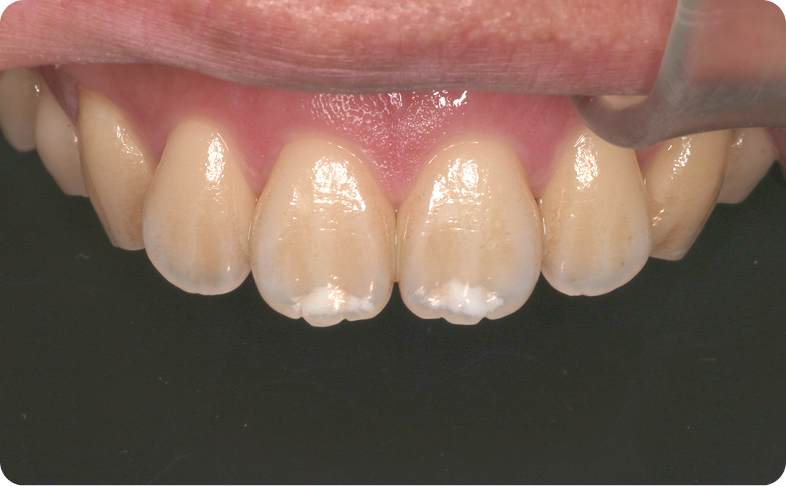

交差している歯並びを改善しました

BEFORE

交差した歯並びの治療前

AFTER

交差した歯並びの治療後

年代・性別

8歳 女の子

主訴

前歯の歯並びが気になる

診断

骨格性Ⅰ級、歯性Ⅰ級、前歯部クロスバイト(一部)、前歯部叢生

治療内容

拡大床(弾線付き)、部分的な唇側ワイヤー矯正、リテーナー

治療期間

2年半

治療リスク

痛み、歯根吸収

治療費用

約40万円